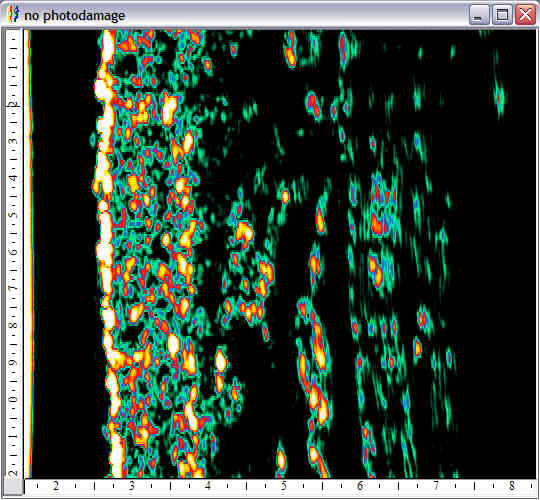

| Aging |  Face, no photoaging |